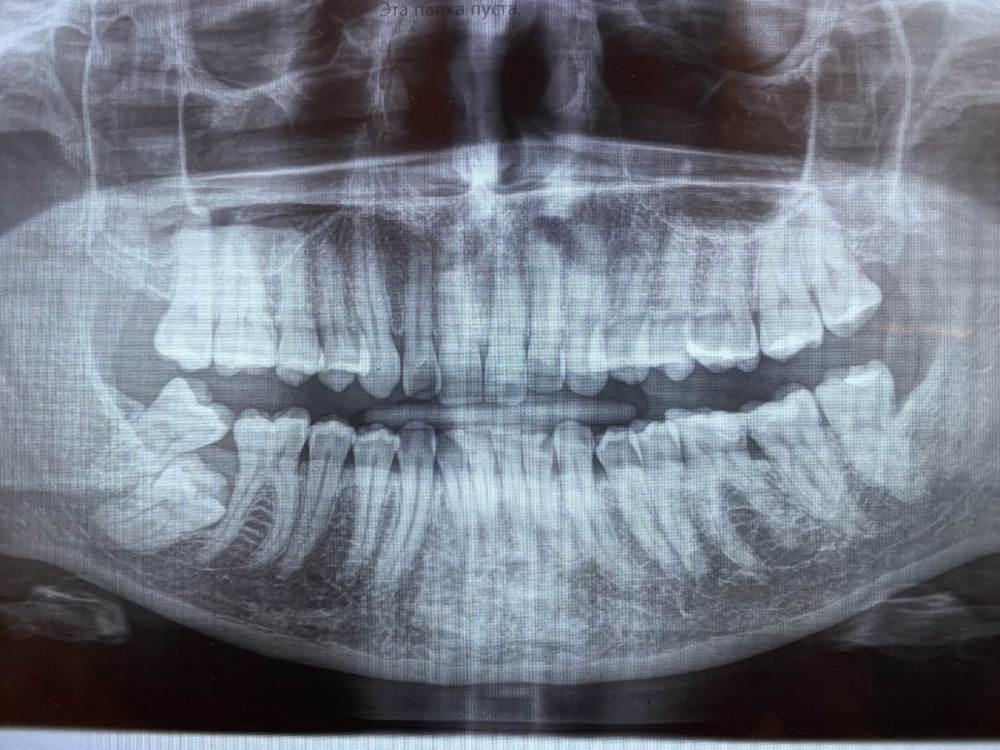

уважаемые врачи, подскажите ваши варианты решения вопроса с застрявшей 7кой?

КТ еще не делали, нечаянно недавно обнаружили на снимке 7ку. После снимка делали чистку, не помню как называется, которая под деснами прям и врач сказала что при надавливании на место между 6 и 8 выходил хлопьями гной, как бы старый уже, она чем-то промыла там как смогла. До чистки ничего не беспокоило.

рентген зубов.jpg